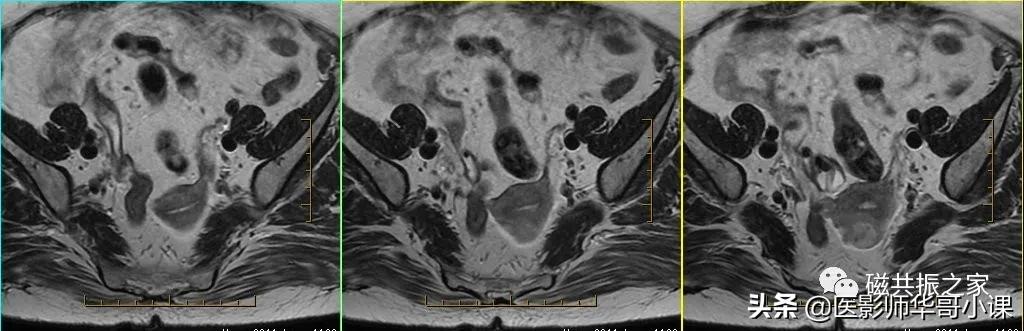

横断面: AX T2WI FSE 横断面T2加权序列

在冠状位和矢状位上定位,在矢状位上找到显示子宫全景最好的层面,如需了解宫颈病变,使定位线垂直于宫颈管长轴(图A),如需了解子宫内膜病变,使定位线垂直于子宫内膜长轴(图B)。在冠状位调整角度使两侧对称扫描,扫描范围上至子宫上缘下至耻骨联合,需包括整个病变范围,如观察转移性病变需加大扫描范围。

相位编码方向为左右方向,采用过采样技术。

添加上下饱和带,减小血管搏动伪影。

该序列是建议扫描子宫必须要有的序列。

T2WI是评估子宫肌层浸润深度的关键序列。 序列常采用小视野的高分辨率扫描。